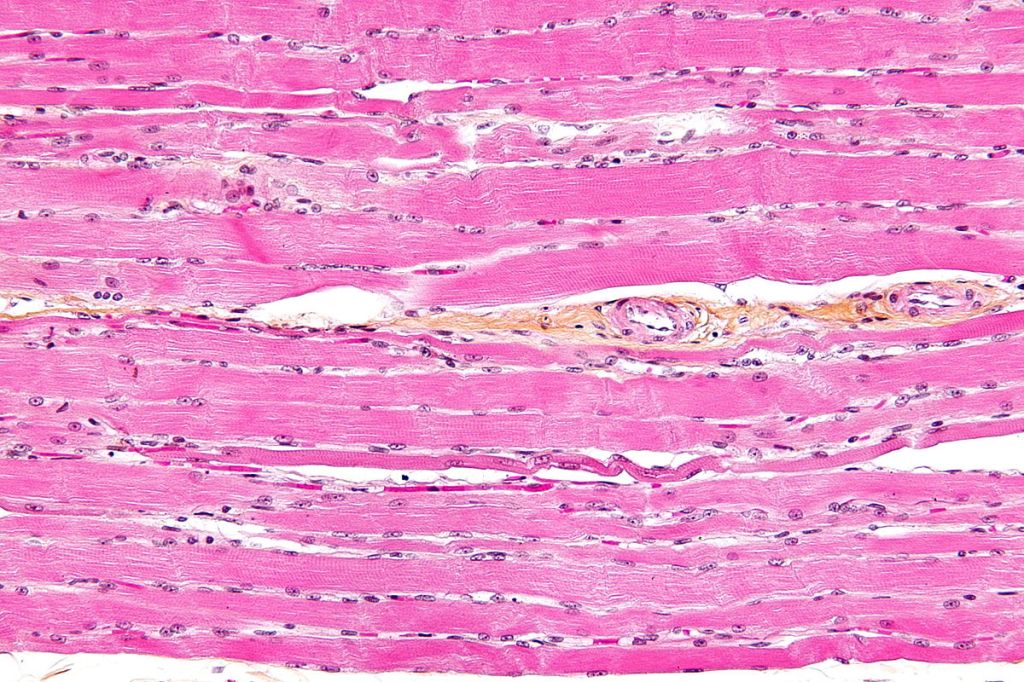

As a reminder, cells are relatively large entities in the range of tiny things of which the body is composed. They have a complex architecture, made up of a large number of discrete parts, known collectively as organelles – little organs – each with its own distinctive function. As in a town or city, the many diverse structures inside a cell look and behave in different ways, but they interact together to make the whole system work. A previous blog gives some insight into this: Very small and very busy: inside the cell. Cells vary in size. On average they are 10 – 100 micrometres across; about ten would fit across the width of a human hair. The also vary radically in shape. Nerve cells are an extreme case, having a very elongated arm projecting out of the main body (called an axon) which may reach centimetres or even metres – to reach the distant parts of your body. The variety of form and function is hardly surprising, given the widely varying task they have to perform – from carrying oxygen in your bloodstream to tensing up and relaxing your heart muscles. Figures 1, 2 and 3 are examples:

| Figure 1 Nerve cell (green) Figure 2 three kinds of blood cell Figure 3 muscle cells |